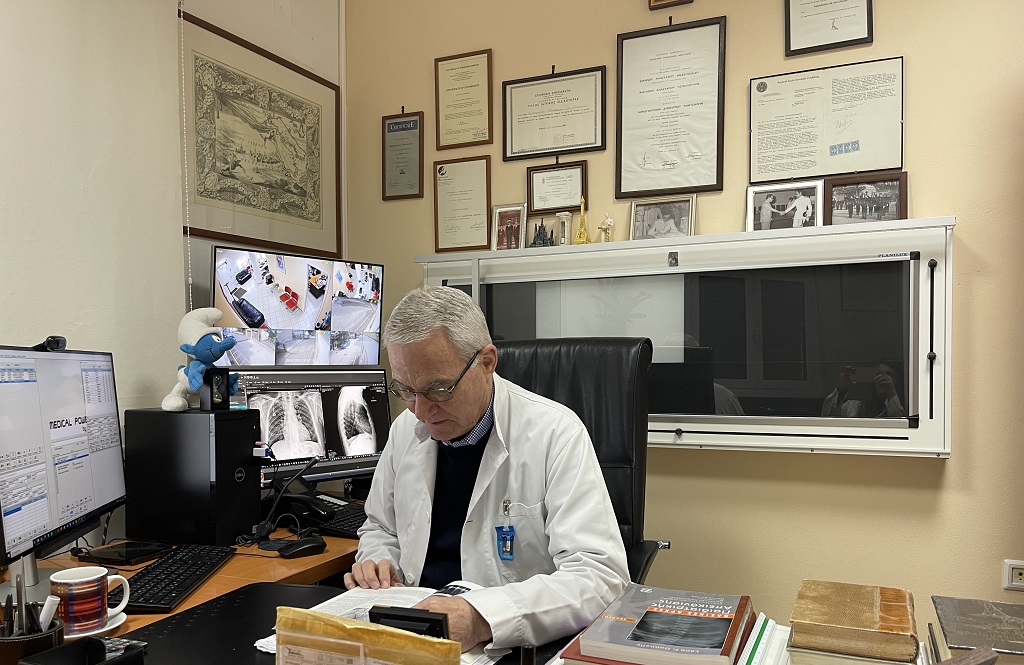

Ἡ ἀκτινολογικὴ ὅμως εἰκόνα (εἰκ. 2) ἦταν ἀρκετὰ ἐνδιαφέρουσα: πολλαπλές περιφερικὲς πνευμονικὲς διηθήσεις, ἄτονες ἢ μόλις ὑποσημαινούμενες, προσομοίαζαν ἀρκετὰ στὸν βιβλιογραφικὸ ὅρο «δίκην θαμβῆς ὑάλου». Ἡ ἐλαφρὰ αὔξηση τῆς ἀκτινολογικῆς πυκνότητος τοῦ πνευμονικοῦ παρεγχύματος στὰ ἐν λόγω διηθήματα ἐπέτρεπε νὰ διατηρεῖται ἡ ἀπεικόνιση τῶν βρογχικῶν καὶ ἀγγειακῶν πρέμνων, γεγονὸς ποὺ σὲ καμμία περίπτωση δὲν ἀφηνε νὰ ἐμφιλοχωρήσει στὴν σκέψη μας ἀκόμη καὶ ἡ παραμικρὰ ἀμφιβολία περὶ ὑπάρξεως πυκνώσεως τοῦ τύπου τῆς κλασσικῆς ἢ συμβατικῆς πνευμονίτιδος, δεδομένου ὅτι στὴν τελευταῖα συσκοτίζεται ἡ ἀπεικόνιση τῶν ἀγγείων, ὄχι ὅμως καὶ τῶν βρόγχων, ἡ ἀπεικόνιση τῶν ὁποίων διατηρεῖται καὶ περιγράφεται μὲ τὸν ὅρο ἀεροβρογχόγραμμα.